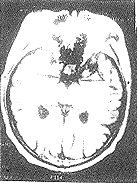

1.2 方法 采用Siemens1.0T和GESignHorizon1.5T超导型MR扫描机,标准头部表面线圈。常规横轴位扫描,用自旋回波序列,T1TR/TE=500/14ms或500/11ms,T2TR/TE=2000/15,层厚8mm,层间距5mm12层,矩阵256×256。在横轴位T1加权图像上取上池层面测量颞叶钩回间距(图1、图2)和经大脑脚层面测量大脑左右径,并计算颞叶钩回间距/大脑左右径比值。

图1 正常老年对照组(左图)

颞叶钩回间距正常(长箭头),大脑左右径(短箭头)